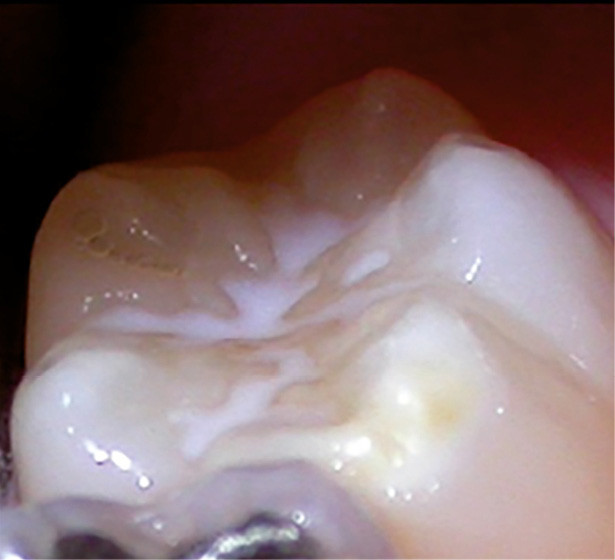

L'hypominéralisation des molaires et des incisives, souvent abrégée en MIH (Molar Incisor Hypomineralization), est une affection dentaire touchant particulièrement les enfants L'hypominéralisation des incisives et molaires, connue sous l'acronyme MIH, est une condition qui compromet la qualité de l'émail dentaire et peut avoir des conséquences importantes sur la santé bucco-dentaire Apprenez ce qu'est la MIH, cette maladie des dents de l'enfant et pourquoi une prise en charge rapide peut éviter des complications.

MIH et AMÉLOGENÈSE Espace Dentaire Béziers. Du diagnostic aux soins, lisez ce guide pour tout savoir sur ce défaut de structure de l'émail des dents. L'hypominéralisation des incisives et molaires, connue sous l'acronyme MIH, est une condition qui compromet la qualité de l'émail dentaire et peut avoir des conséquences importantes sur la santé bucco-dentaire

JCM Free FullText Treatment Approaches to Molar Incisor Hypomineralization A Systematic Review. Qu'est-ce qu'une "molaire incisive hypominéralisation (MIH)" ? C'est une anomalie de la dent Apprenez ce qu'est la MIH, cette maladie des dents de l'enfant et pourquoi une prise en charge rapide peut éviter des complications.